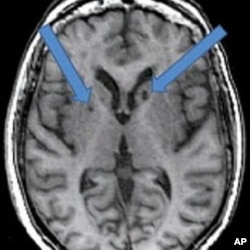

In this scan of a patient who has had two strokes, the arrows point to dark holes filled with fluid. Neuropsychologist Adam Brickman at the Columbia University School of Medicine, says these dark spots were once healthy cells killed by blood clots traveling to the brain.